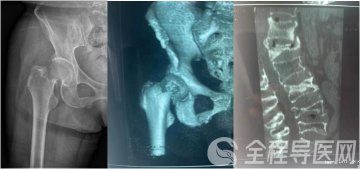

检查结果显示,谢某的身体状况良好,但骨折情况却相当严重。除了右侧股骨颈骨折伴有错位外,还有胸10、胸12、腰1、腰3和腰5等5个椎体的新鲜骨折。面对如此严重的多发骨折,传统的手术方式显然不是最佳选择,因为就算是年轻人也难以承受长时间的手术和麻醉。针对这一特殊情况,张镇提出了分多次进行微创手术的方案。这样既可以减少手术对患者身体的负担,又能达到最佳手术治疗效果。

按照术前计划,谢某首先接受了腰麻下的股骨颈骨折闭合复位空心钉内固定术。手术过程非常顺利,四十分钟便完成了。术后观察期间,医生为她进行了精心的后续治疗。病情稳定后,又为谢某做了两次腰椎骨折的微创手术。每次手术过程都是同样短暂,但效果极佳。局部麻醉的运用,谢某在手术过程中几乎感觉不到任何痛苦。

虽然术后的X光片看起来令人触目惊心,但实际上,这些复杂的手术都是通过微小的切口完成的。最大的伤口只有1公分大小,最多只需缝合一针。而背部的切口更是小得如同“小眼”一般,无需缝合和拆线。大约一周后,谢某就可以自行移除纱布了。